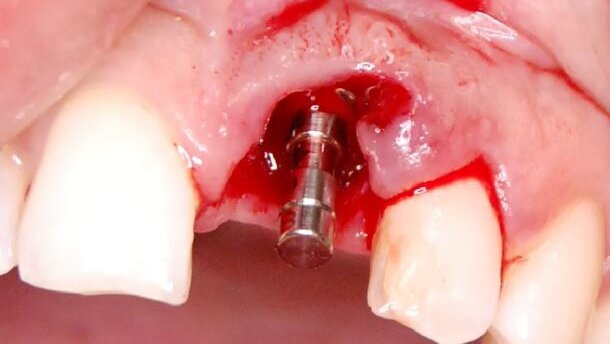

W znieczuleniu nasiękowym Ubistesin Forte (3M ESPE) nacięto ostrzem 15C szczelinę dziąsłową wokół korony zęba 21 oraz dziąsło wokół wydzielającego się przez tkanki fragmentu. Koronę zęba wraz z wkładem usunięto kleszczami, wydzielający się fragment pęsetą, a pozostałą część korzenia wąskim luksatorem (Ryc. 4). Zębodół wyłyżeczkowano i przepłukano 0,5% metronidazolem (Polpharma). W czasie usuwania wydzielającego się fragmentu korzenia doszło do uszkodzenia dystalnej brodawki dziąsłowej.

Wypreparowano łoże pod implant TSIII 4,0 x 11,5 (Osstem Implants) (Ryc.6). Przygotowano pod względem kształtu membranę nieresorbowalną Cytoplast TXT-200 z d-PTFE (Osteogenics Biomedical), którą szwem materacowym Cytoplast PTFE 4,0 (Osteogenics Biomedical) wprowadzono pod płat śluzówkowo-okostnowy, powyżej ubytku kostnego od strony przedsionka i ufiksowano. Ubytek kostny wypełniono materiałem kościozastępczym CompactBone B (Dentegris GmbH). Implant wszczepiono i zamknięto śrubą zamykającą (Ryc.7). Membranę poprowadzono ponad zębodołem. Brzegi boczne wprowadzono pod tkankę miękką mezjalnie i dystalnie od zębodołu, a drugi koniec szwem materacowym wprowadzono pod delikatnie odwarstwiony płat od strony podniebienia. Dystalną brodawkę dziąsłową zbliżono szwem (Ryc. 8 i 9). Wykonano kontrolne badanie rtg, potwierdzające prawidłowe pozycjonowanie implantu (Ryc.10). Brak zębowy zaopatrzono wcześniej przygotowaną pracą czasową (Ryc. 11). Po zabiegu pacjentka przyjmowała antybiotyk i leki przeciwbólowe.